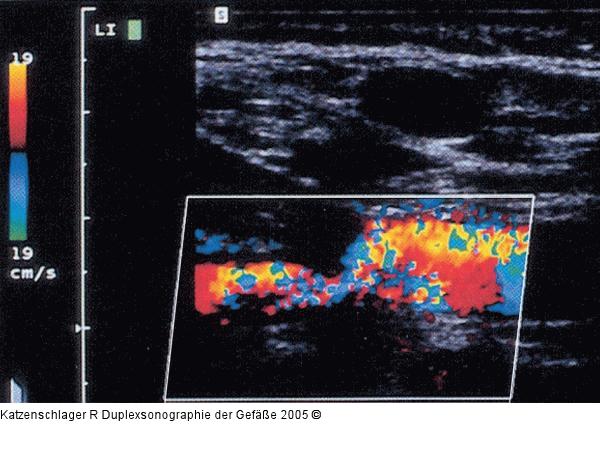

Abbildung 6: Duplexsonographie - A. subclavia

Hochgradige Stenose der A. subclavia |